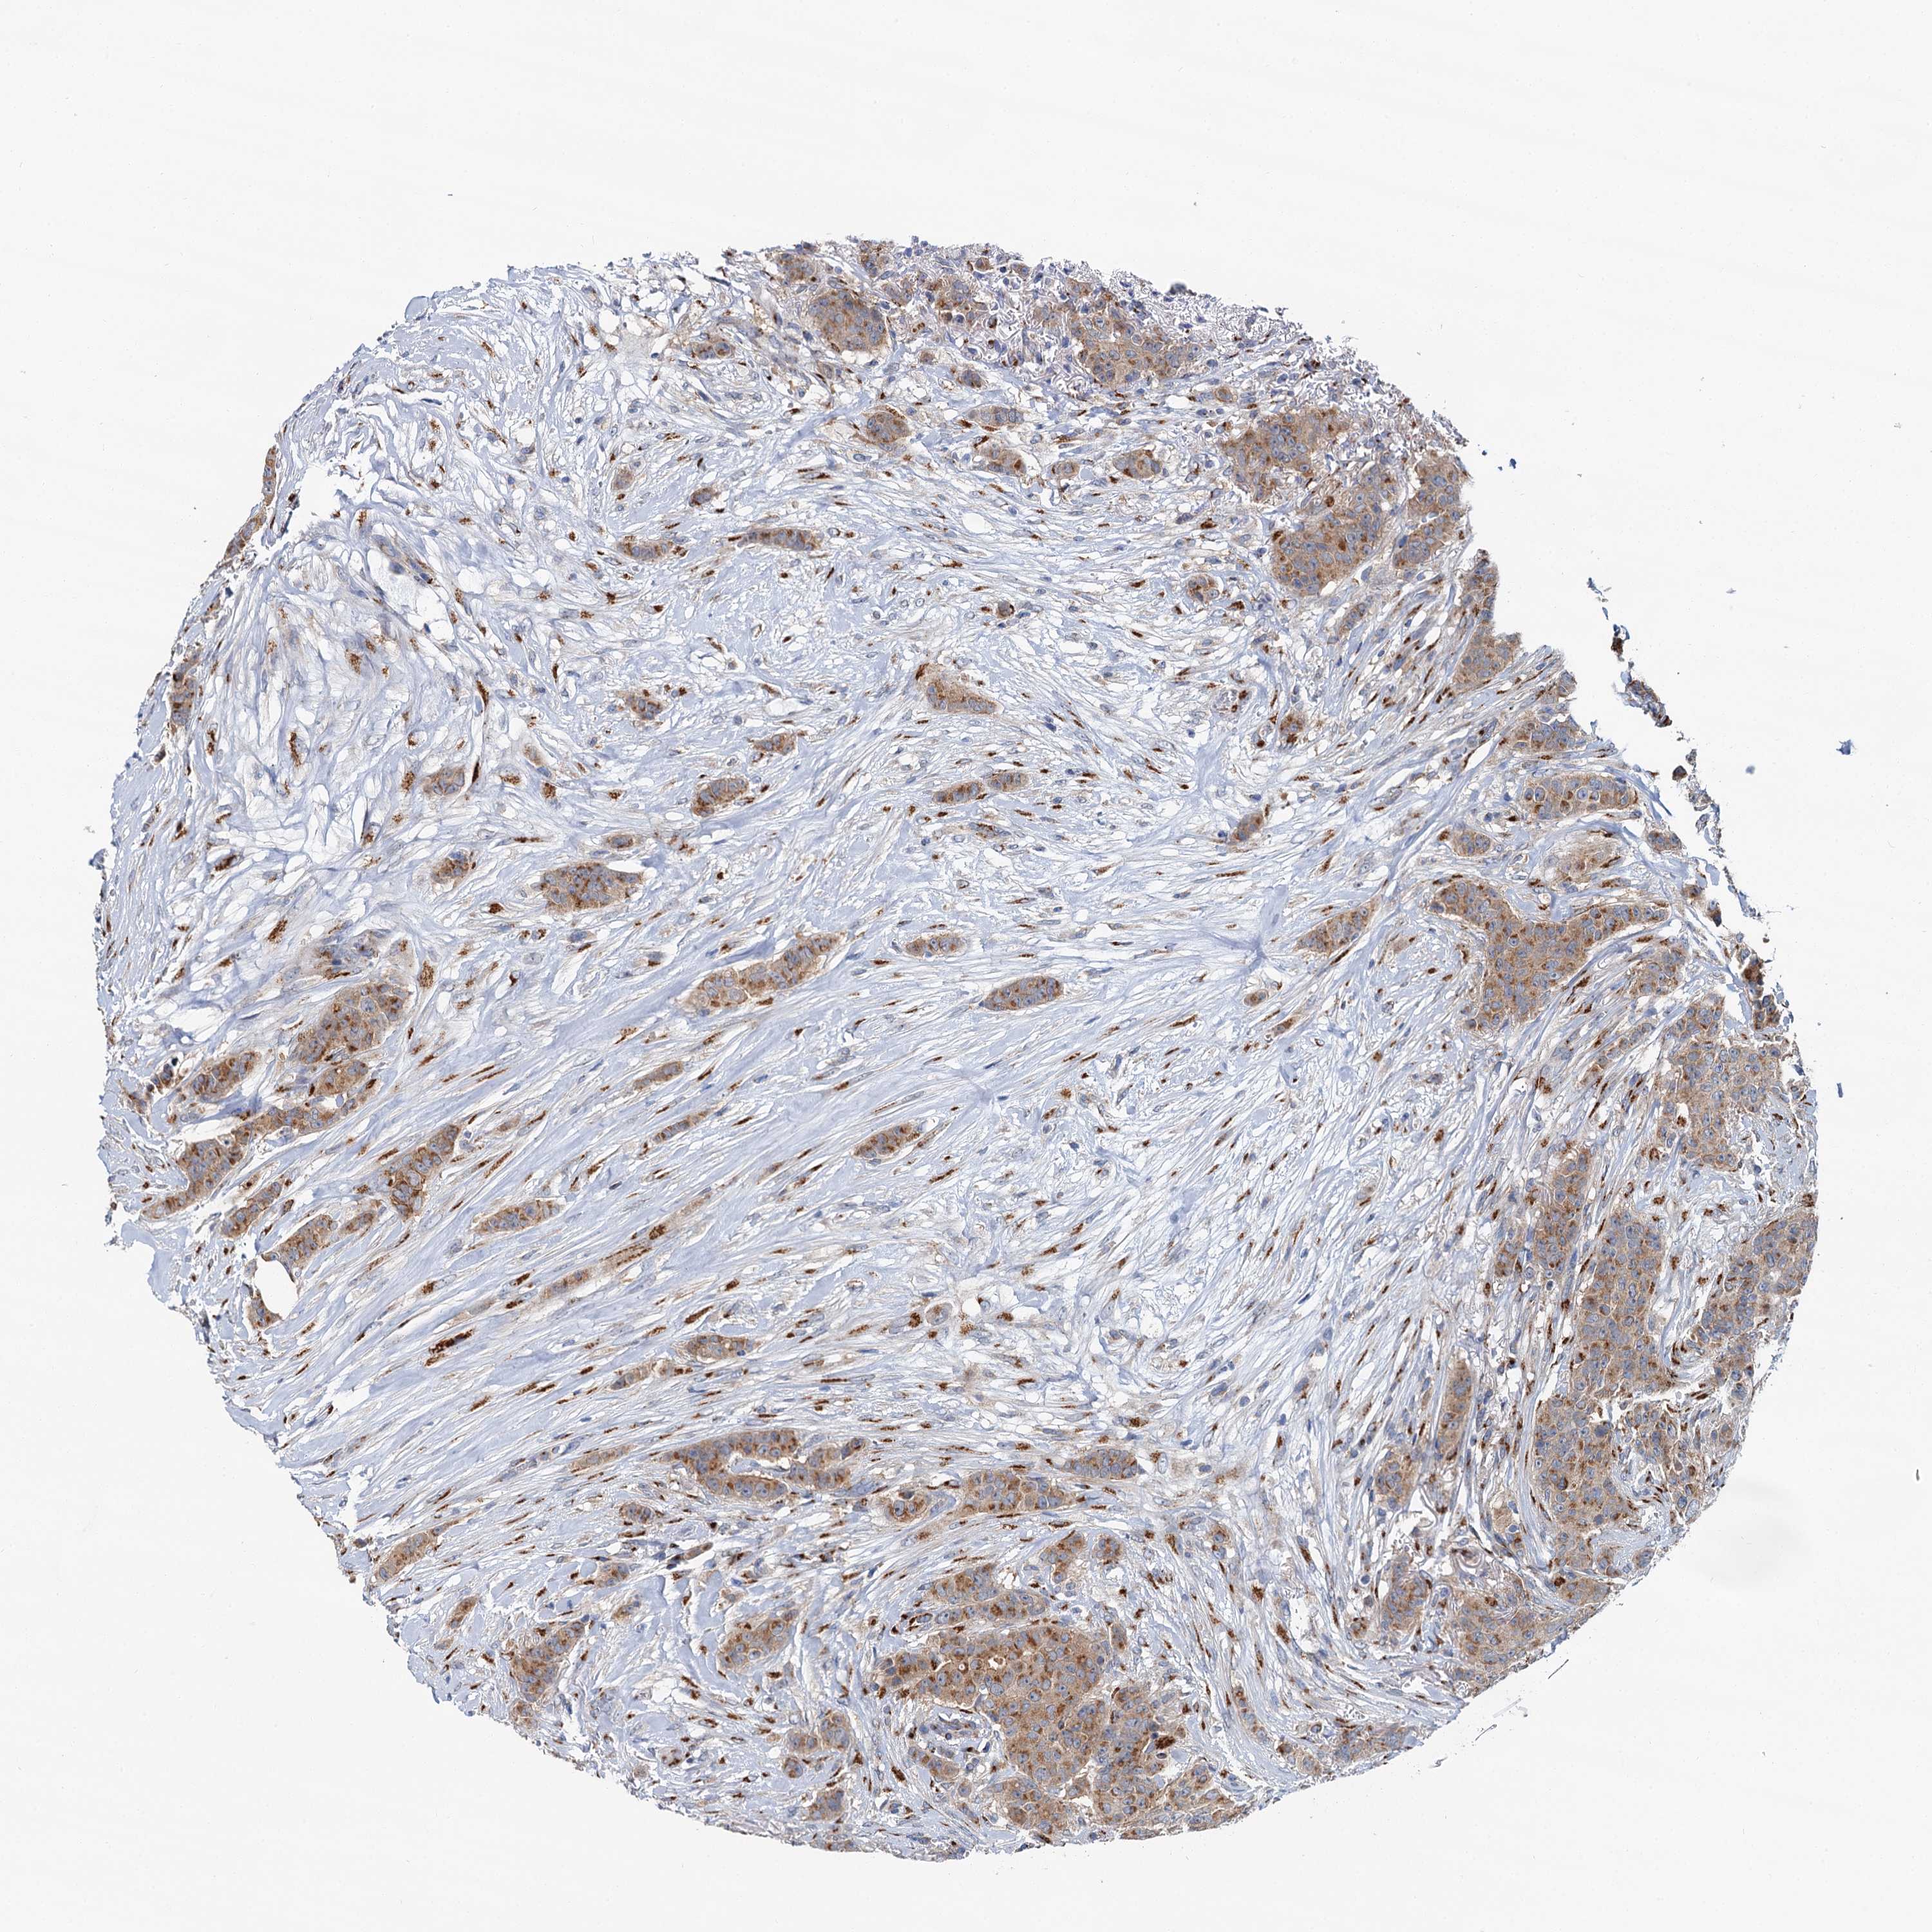

BRCA TCGA BRCA VALIDATION PROTEIN EXPRESSION